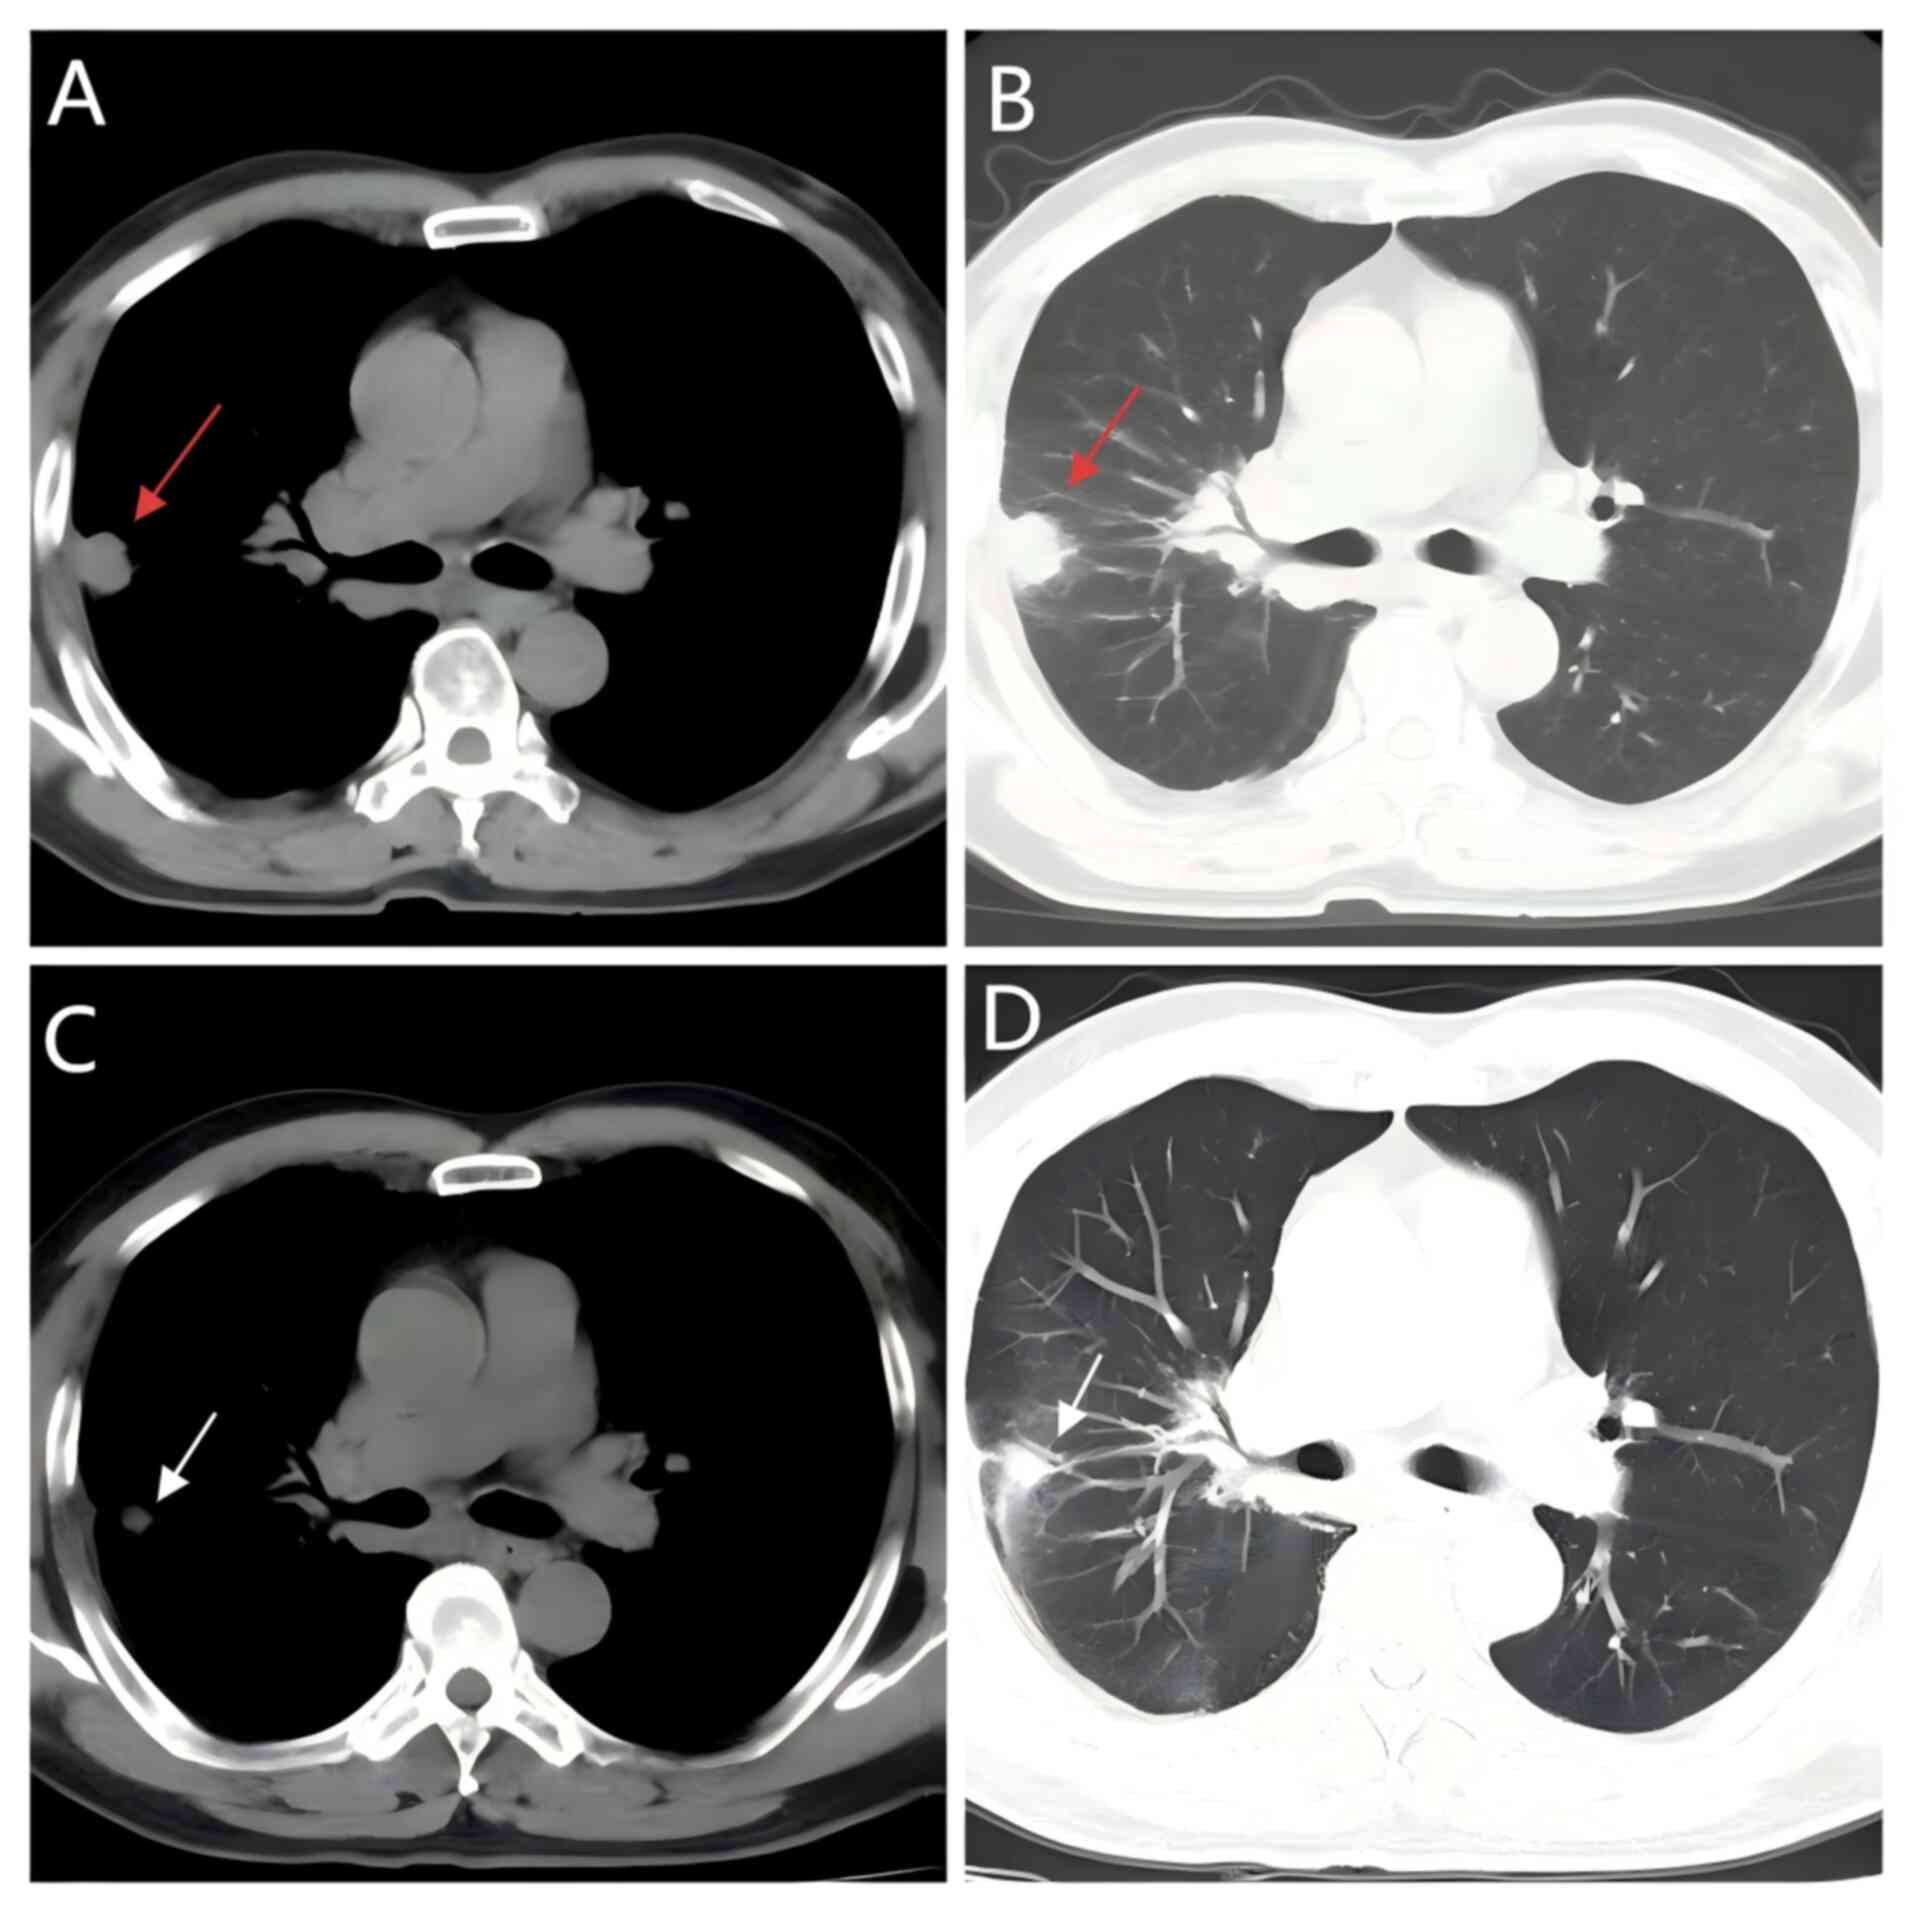

Figure 6

Axial chest CT scans before and after

treatment. (A) Pre-treatment CT (mediastinal window) reveals a

heterogeneously enhancing mass (46×35 mm) in the right lower lung

lobe with suspected malignant pleural effusion and right

hilar/mediastinal lymphadenopathy (red arrow). (B) Pre-treatment CT

(lung window) reveals decreased aeration in the right lower lobe

due to compression by the mass, along with visible pleural

effusion. (C) Post-treatment CT (mediastinal window) reveals

reduction in the mass size, resolution of pleural effusion, and

improved lung clarity in the right lower lobe (white arrow). (D)

Post-treatment (lung window) reveals improved lung clarity in the

right lower lobe and re-expansion of the compressed lung tissue,

with no evident pleural effusion.